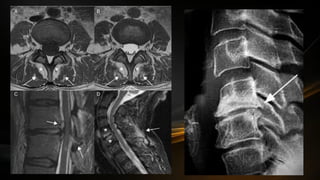

Raíces nerviosas y segmentos medulares

• Hay 31 pares de nervios espinales o raquídeos

• Cada nervio espinal esta formado a la medula espinal por una raíz

posterior de carácter sensitivo y una raíz anterior de naturaleza

motora

• Las fibras posteriores penetran en el surco posterolateral y por el

surco anterolateral salen fibras para construir la raíz anterior

• Las raíces dorsales contienen el ganglio espinal, donde se encuentran

los cuerpos de las primeras neuronas que recogen la sensibilidad

somatoestesica del tronco y extremidades

• La distribución de nervios espinales es la siguiente: 8 cervicales, 12

torácicos, 5 lumbares, 5 sacros y 1 coccígeo

• Existen los segmentos medulares que indica que porción de la medula

proporciona nervios a una determinada zona

• A nivel de la porción caudal de la medula la mayoría de nervios

lumbares, sacros y coccígeo descienden de forma que dan aspecto de

cola de caballo